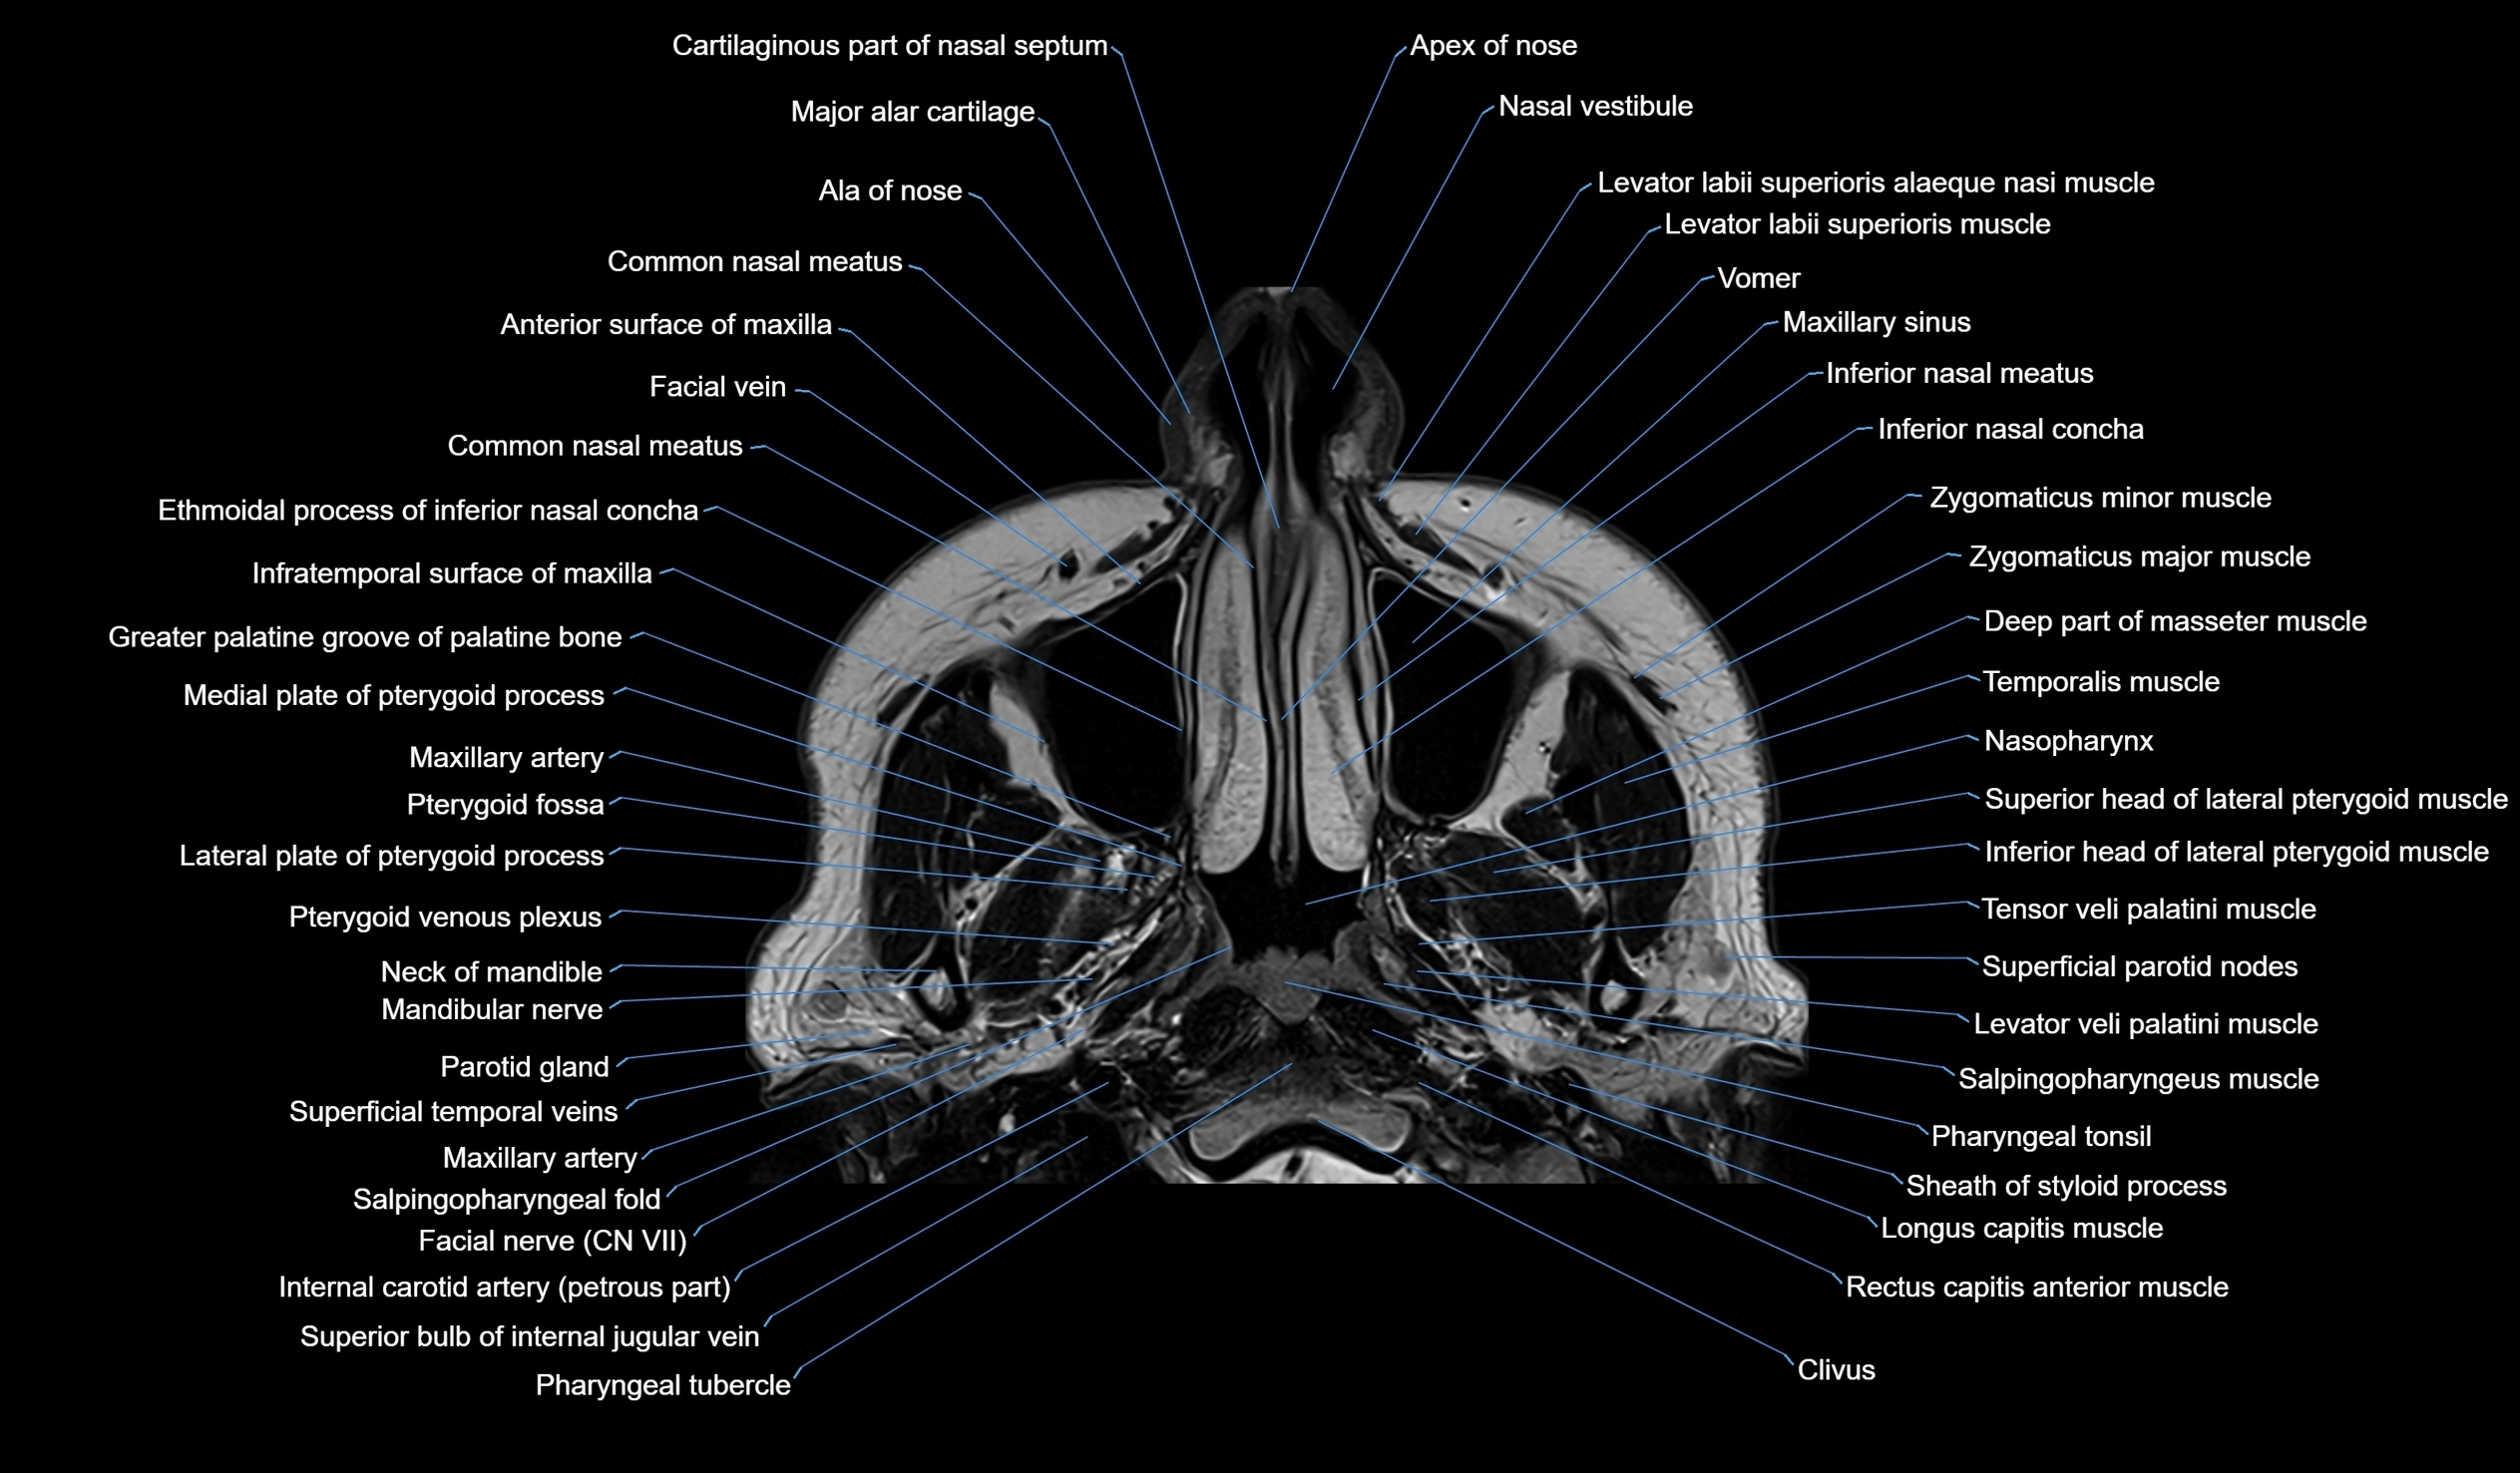

MRI images